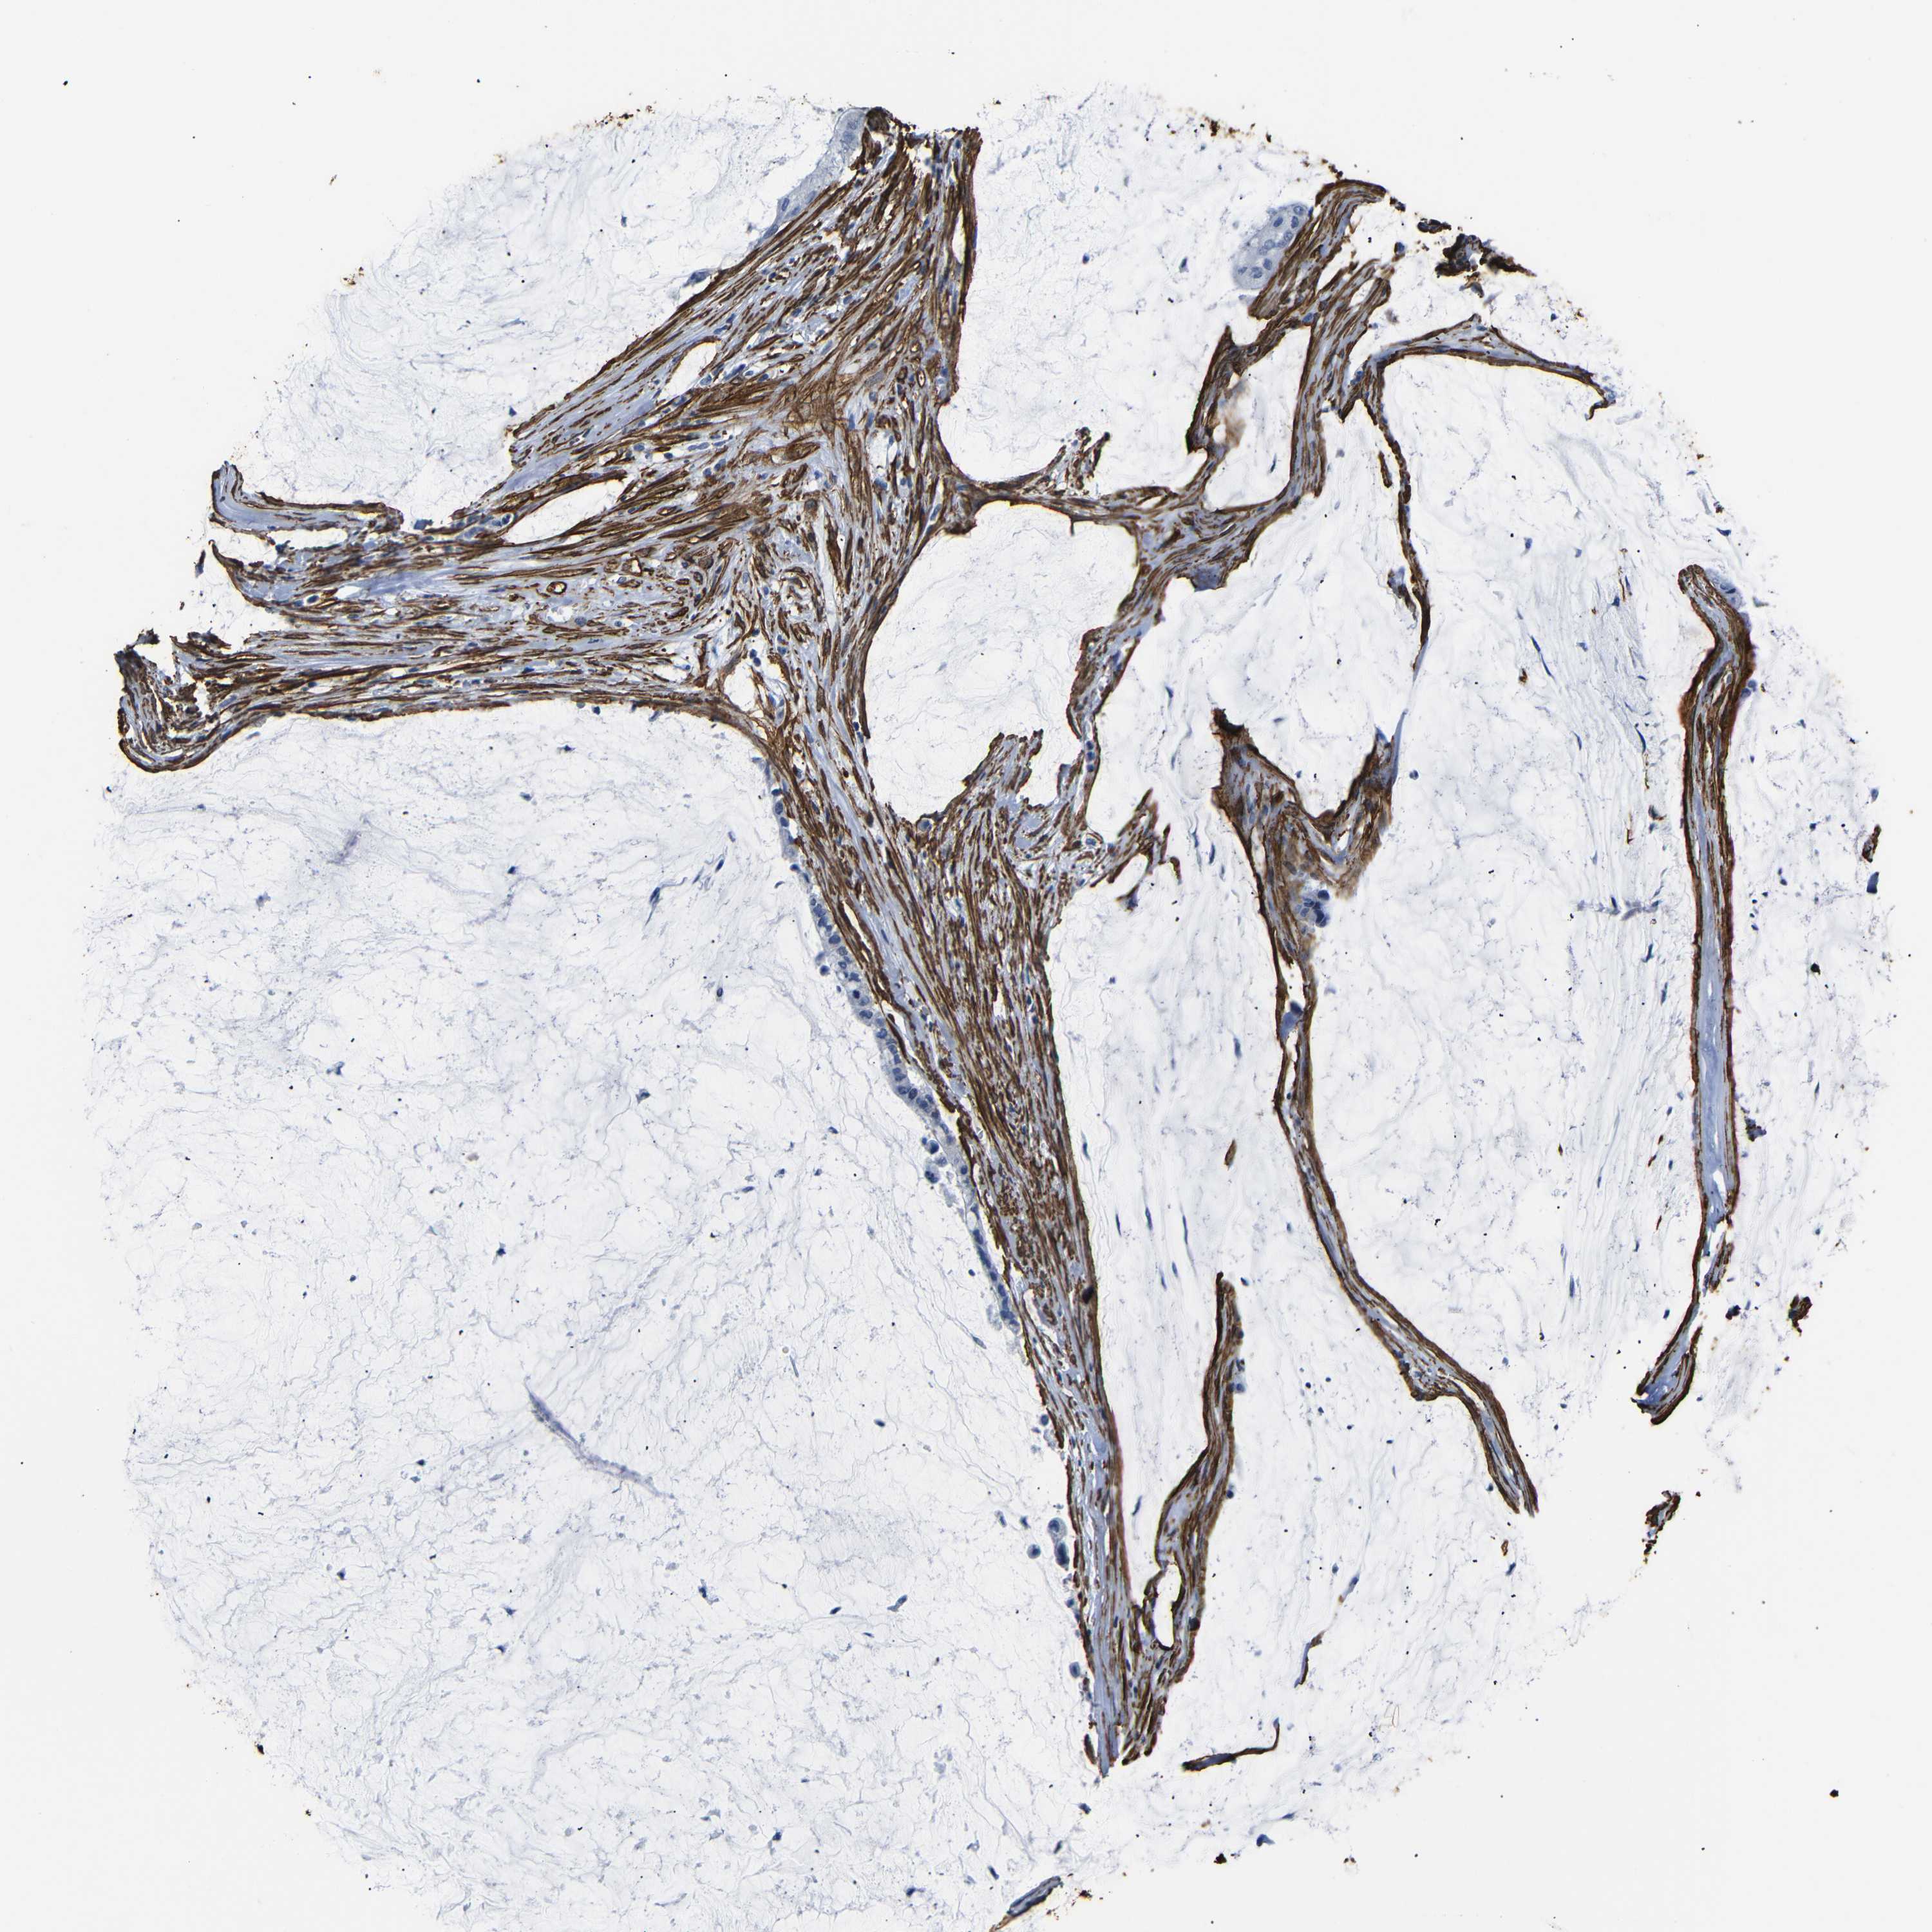

PANCREATIC CANCER - Protein expressioni

A mouse-over function shows sample information and annotation data. Click on an image to view it in a full screen mode. Samples can be filtered based on level of antibody staining by selecting one or several of the following categories: high, medium, low and not detected. The assay and annotation is described here.

Note that samples used for immunohistochemistry by the Human Protein Atlas do not correspond to samples in the TCGA dataset.

Antibody stainingi

Antibody staining in the annotated cell types in the current human tissue is reported as not detected, low, medium, or high, based on conventional immunohistochemistry profiling in selected tissues. This score is based on the combination of the staining intensity and fraction of stained cells.

Each image is clickable and will lead to virtual microscopy that enables deeper exploration of all samples and also displays staining intensity scores, fraction scores and subcellular localization as well as patient and tissue information for each sample.

HPA041264

HPA041271

CAB000002

CAB003761

CAB013531

Staining

High

Medium

Low

Not detected

Intensity

Strong

Moderate

Weak

Negative

Quantity

>75%

75%-25%

<25%

None

Location

Nuclear

Cytoplasmic/membranous

Cytoplasmic/membranous,nuclear

Adenocarcinoma, NOS